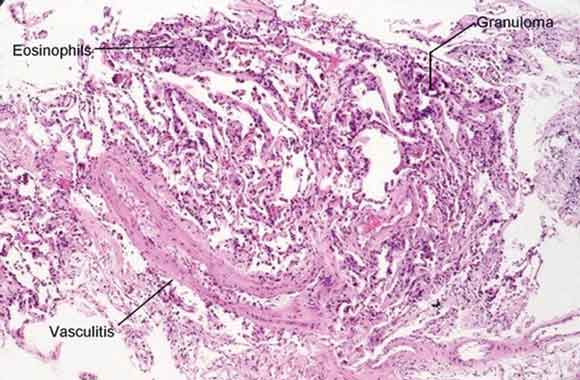

A chest x-ray demonstrated bilateral ground glass infiltrates, predominantly in the basal zones. High-resolution computed tomography (CT) of the chest revealed bilateral patchy ground glass opacities (Box 1). Spirometry showed a forced vital capacity (FVC) of 65% predicted, a forced expiratory volume (FEV1) of 68% predicted, and FEV1/FVC of 104%. An echocardiogram was normal. A nerve conduction velocity study showed axonal involvement, with reduced nerve conduction velocity in the right radial and left superficial peroneal nerves. CT of the paranasal sinuses showed chronic pansinusitis. Histopathological examination of the open-lung biopsy showed leukocytoclastic vasculitis, granuloma formation, and extravascular eosinophilic infiltration (Box 2). Renal biopsy showed pauci-immune, crescentic glomerulonephritis. Renal vessel Doppler ultrasonography and renal angiography gave normal results and ruled out any renal vessel involvement. The patient tested positive for perinuclear antineutrophilic cytoplasmic antibodies (ANCAs) and negative for cytoplasmic ANCAs by the indirect immunofluorescence method. A more specific enzyme-linked immunosorbent assay (ELISA) for anti-myeloperoxidase was positive, and another, for anti-proteinase 3, was negative. These tests ruled out Wegner’s granulomatosis. Antinuclear factor, anticardiolipin antibodies, hepatitis B surface antigen, and serological tests for hepatitis C and HIV were negative, thus ruling out significant secondary causes of vasculitis.